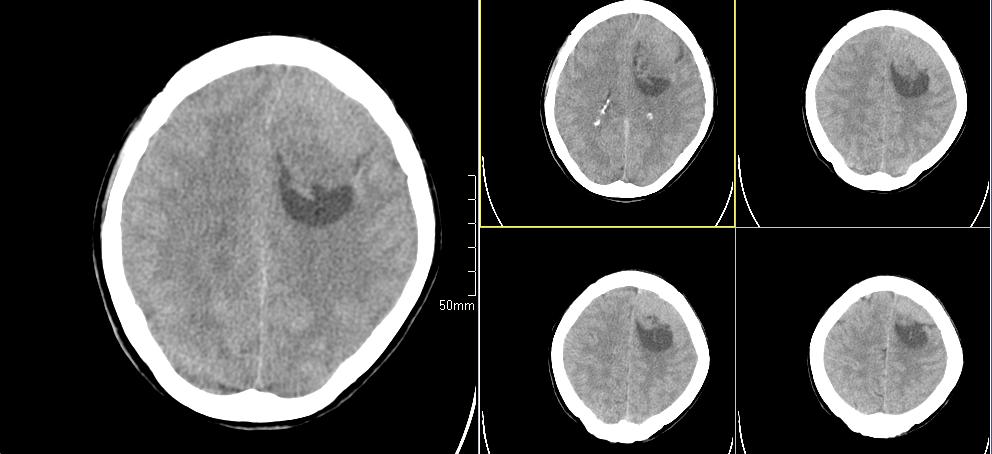

标题: CT23966:女,34岁,近一月头痛、意识障碍 [打印本页]

标题: CT23966:女,34岁,近一月头痛、意识障碍

左侧额叶见不规则软组织影,部分囊变,病变略呈等密度,占位效应明显,考虑血母可能。脑膜瘤不除外

左侧额叶肿瘤样病变,成等密度,其内可见囊变,肿瘤似与大脑镰相连,周围水肿不明显。考虑脑膜瘤可能!建议强化或mri。

左额叶囊实性肿块,实性部分呈等密度,密度不均,考虑胶质瘤可能性大,脑膜瘤及室管膜瘤不除外,建议mri增强扫描。

左额叶较大等低混杂密度影,占位效应明显,首先考虑:左额叶胶质瘤。

左侧额叶肿瘤性病变(胶质瘤?);建议行进一步检查。